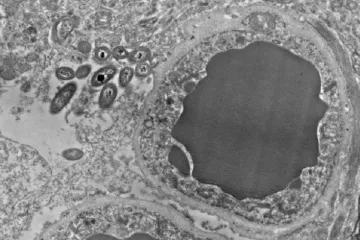

SMRT IZ DRUGOG KUTA / Snimali su mozak umiruće osobe: Kad je izdahnula, EEG je podivljao! Čudnovate pojave iznenadile i liječnike